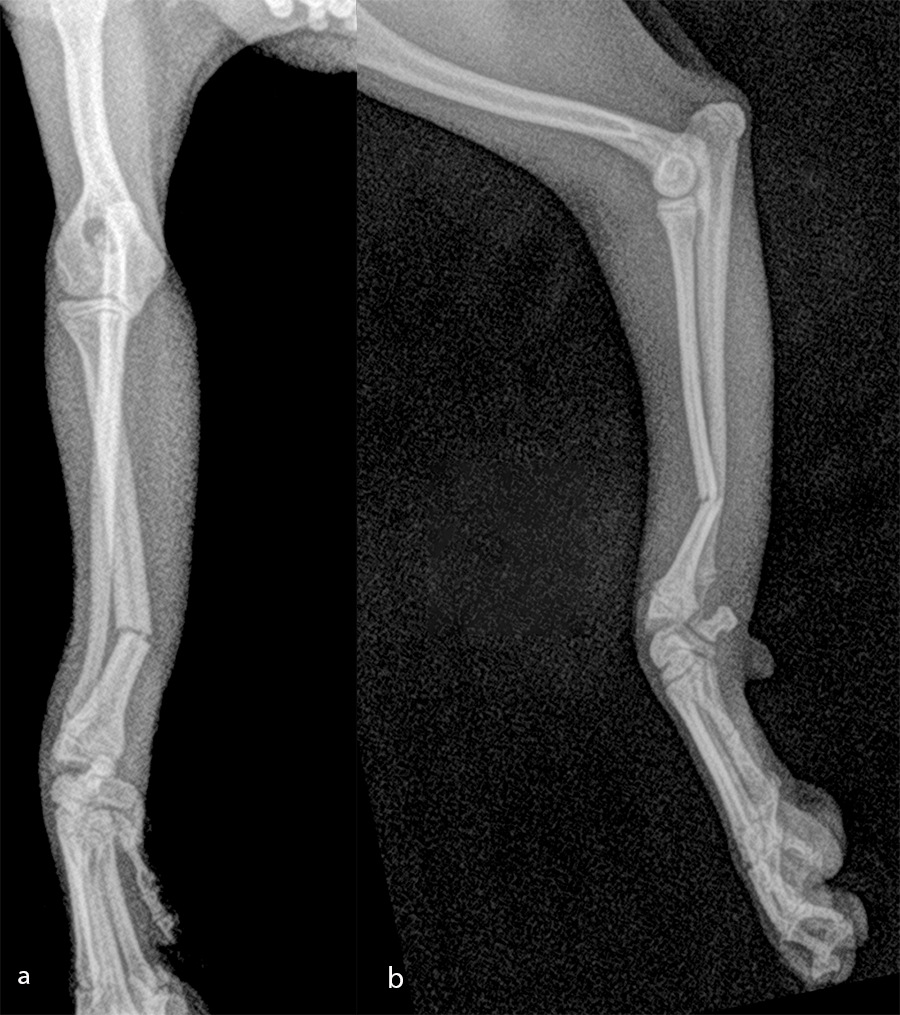

The patient was a 6-month-old, 1 kg (exactly 0.950 kg) Pomeranian dog presenting with a radial fracture of the left thoracic limb after a jump from ≈ 50 cm. The 1.5 mm System was too large for the width of the radius (2.2 mm) and the width of the radial medullary canal (0.5 mm) (Fig 7). The 1.3 mm adaptation plate was a perfect plate for this fracture. This plate option permitted the use of cortex and locking screws.